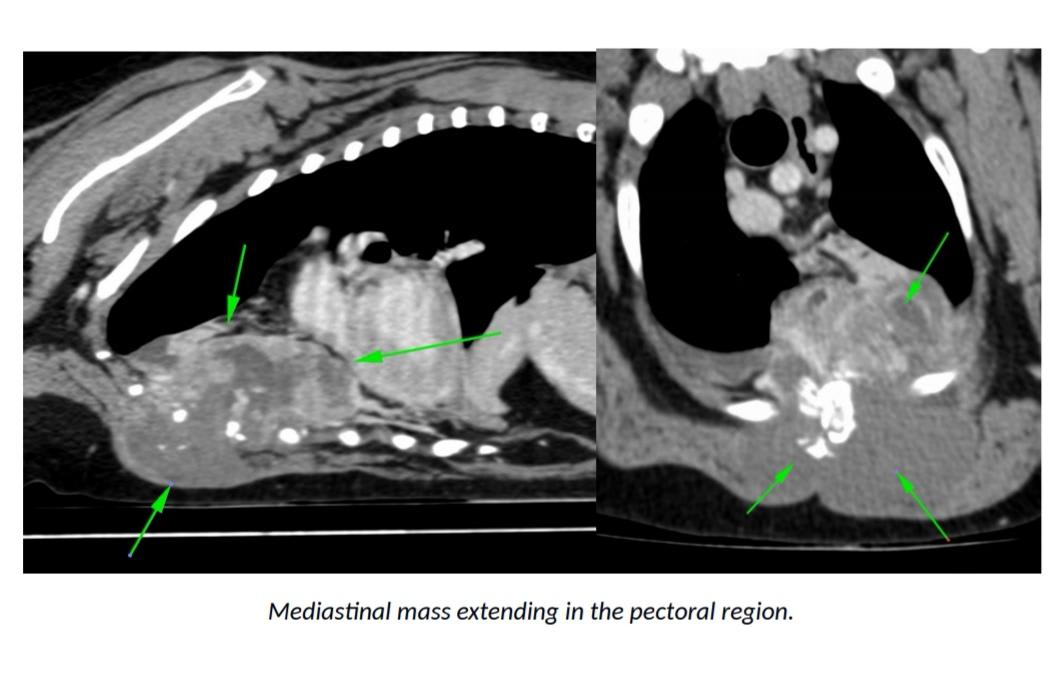

Hello. Yogi has this mass on his chest with nodules in his lung lobes and liver. He is however acting completely normal, going on walks, eating and in no apparent discomfort. He subsequently isn't currently on any medications. Is this normal? And should we expect him to go downhill soon/in the near future? Should this mass be causing him discomfort? He is breathing fine and doesn't seem to have his initial cough anymore except when overly exerting himself. Many thanks for your time

Thank you for submitting your question regarding Yogi. I am sorry to hear of his recent diagnosis. It is wonderful that he is still feeling well. I do not suspect this will be the case for long, as the mass and fluid will ultimately interfere with his ability to breathe. If treatment is not possible, it will continue to grow. I would suspect this to happen within 1-3 months. You can consider pain medication if his attitude or appetite changes. His veterinarian can prescribe something for him. In the meantime, enjoy all of your time with him.

Thank you for submitting your question regarding Yogi. How frustrating to not have any definitive answers regarding his condition. I am happy to hear that he is still doing well for you at home though. Unfortunately, regardless of the exact cause of his lesions, I suspect that he will begin to deteriorate. The lesions appear extensive and have the possibility to ultimately interfere with his breathing. I encourage you to enjoy him and make as many memories with him as possible. I have had some families created a bucket list of things to do with an aging pet. Best of luck.